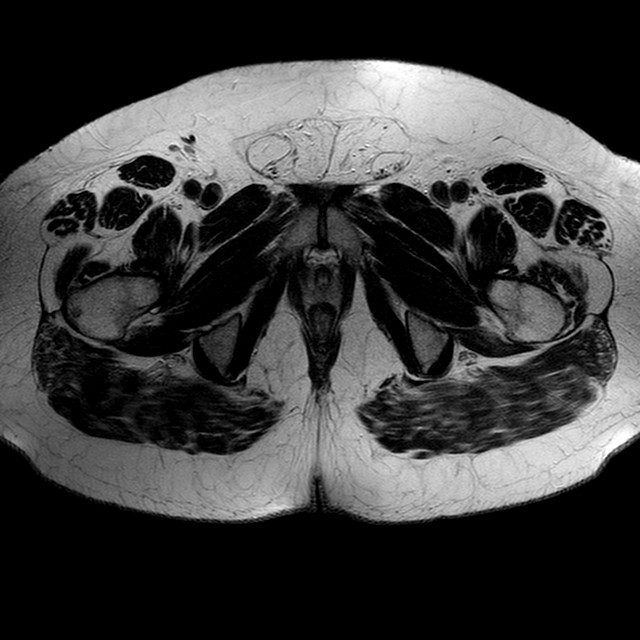

Esami: RMN BACINO

T2w TSE

Evidenti e simmetriche alterazioni osteofitosiche in regione coxo femorale con riduzione delle rime articolari. Degenerazione completa del cercine glenoideo. Non attuali segni di versamento articolare. Non segni di edema osseo che escludono attuale algodistrofia od osteonecrosi. Lieve e simmetrica riduzione del trofismo della muscolatura glutea.